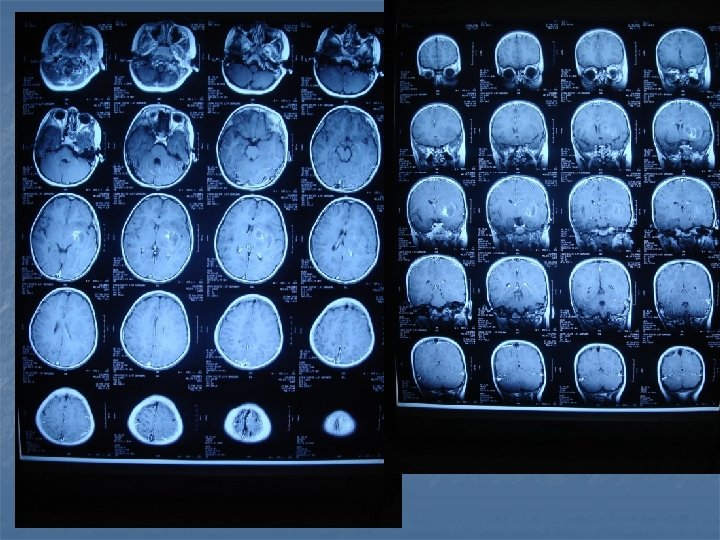

Tüberkülomlar n n İntrensek beyin kitleleri CPA’da, sellar bölgede, kavernöz sinüste, durada da tüberkülomlar tanımlanmıştır. BT’de her türlü lezyonu taklit edebilir. Genellikle izodens kitlelerdir. Çevresel veya homojen kontrast tutarlar. MR’da ise T 1’de hipo veya izointens olup kontrasttan sonra çok iyi boyanırlar. Çok sayıda, yaygın, küçük lezyonlar olarak veya matür tüberkülomlar şeklinde, daha büyük, ortası nekrotik hipointens, çevresi ödemli lezyonlar şeklinde karşımıza çıkabilirler.

Toxoplasmosis n n n Yer kaplayan lezyonların % 60’ı % 30 olguda mevcut Kortikomedüller bileşke (? ), basal ganglion ve talamusda sık tutulum BT-MR. . . >5 lezyon, halka tarzında kontrast (+), nodüler, ödem ve kitle etkisi Erken tanı önemli. . . tedavi edilebilir 2 hafta primethamine+sulfadiazine